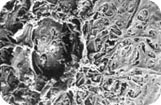

Selective Laser Trabeculoplasty is an improvement over conventional ALT by eliminating thermal damage of the trabecular meshwork architecture.

Using a low-energy, Q-switched, frequency doubled Nd:YAG laser emitting at 532 nm with a pulse duration of 3 nanoseconds, researchers demonstrated isolated destruction of the pigmented TM cells without thermal or collateral damage to the surrounding non-pigmented cells and trabecular collagen beams. Further, endothelial membrane formation on the TM, usually found in ALT-treated eyes, was not observed after SLT exposure in vivo.

Other research using scanning and transmission electron microscopy to compare the acute morphologic changes in the TM of human eye bank eyes after ALT and SLT confirmed these histologic findings. After laser irradiation, ALT produced crater formation, coagulative damage, fibrin deposition and disruption of trabecular beams and endothelial cells. Eyes treated with SLT did not show these findings; the general structure of the TM was preserved. SLT’s effect occurred intracellarly, with disruption of the melanin granules. The lack of thermal and structural damage to the TM makes SLT potentially repeatable.*